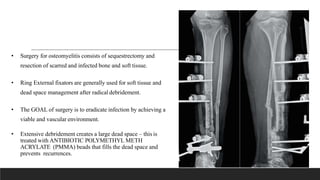

• Surgery for osteomyelitis consists of sequestrectomy and

resection of scarred and infected bone and soft tissue.

• Ring External fixators are generally used for soft tissue and

dead space management after radical debridement.

• The GOAL of surgery is to eradicate infection by achieving a

viable and vascular environment.

• Extensive debridement creates a large dead space – this is

treated with ANTIBIOTIC POLYMETHYL METH

ACRYLATE (PMMA) beads that fills the dead space and

prevents recurrences.